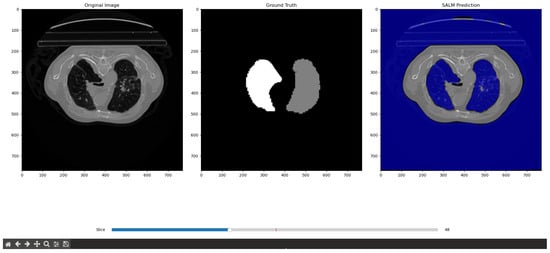

4.2. Qualitative Results